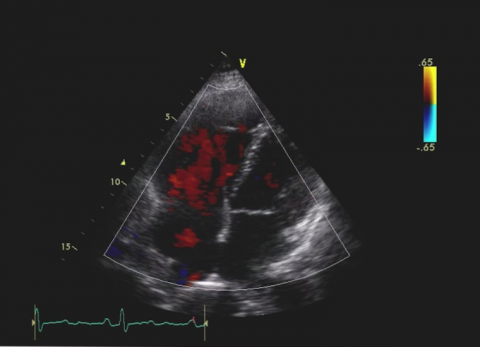

Pułapki Echokardiograficzne. Przypadek 39

dr n. med. Barbara Lichodziejewska

Pień płucny i jego zastawka. Tajemnicze obrazy.